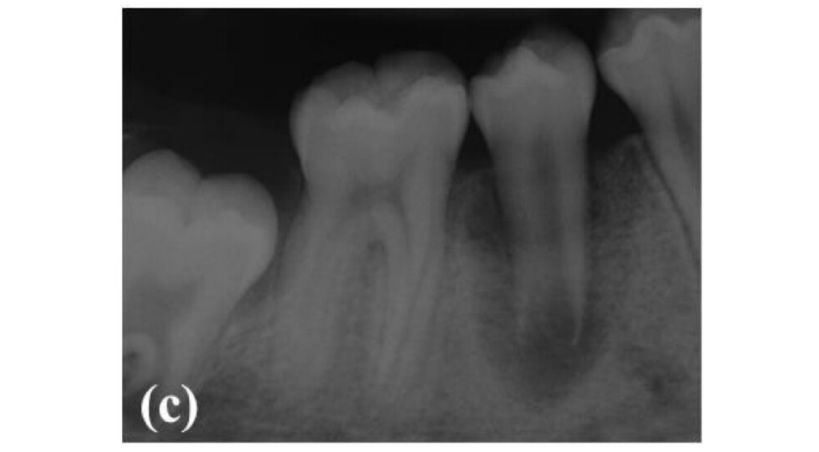

Figura 1. A. Coloración rosada en tercio cervical del 2.1

B. Imagen radiográfica (Patel, 2009)